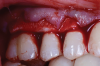

A female patient presented to the practice with generalized gingival recession in the maxilla that extended from tooth No. 4 to tooth No. 13 (her maxillary first premolars were missing). The recession was classified as Cairo RT1 for all affected teeth, and the root exposure ranged from 1 mm to 4 mm. As part of the examination, radiographs were acquired; however, no remarkable interproximal bone loss was observed (Figure 5). Teeth Nos. 4, 6, 10, 11, and 13 were the most severely affected, and NCCLs were present on the canines and premolars (Figure 6). More specifically, tooth No. 4 presented with 3 mm of recession and an NCCL; tooth No. 6 presented with 3 mm of recession and an NCCL; teeth Nos. 7 through 9 presented with 1 mm of recession and no NCCLs; tooth No. 10 presented with 4 mm of recession and an NCCL; tooth No. 11 presented with 4 mm of recession and an NCCL; and finally, tooth No. 13 presented with 3 mm of recession and an NCCL. All of the NCCLs demonstrated a Winter and Allen classification of NCL3. The patient's keratinized tissue was greater than 2 mm for all teeth, her periodontal phenotype was thick, and her midline frenum was prominent and inserted 5 mm apical to the tip of the papilla between teeth Nos. 8 and 9.

(6.) Preoperative retracted view of the generalized gingival recession in the maxilla extending from tooth No. 4 through tooth No. 13.

Figure 6